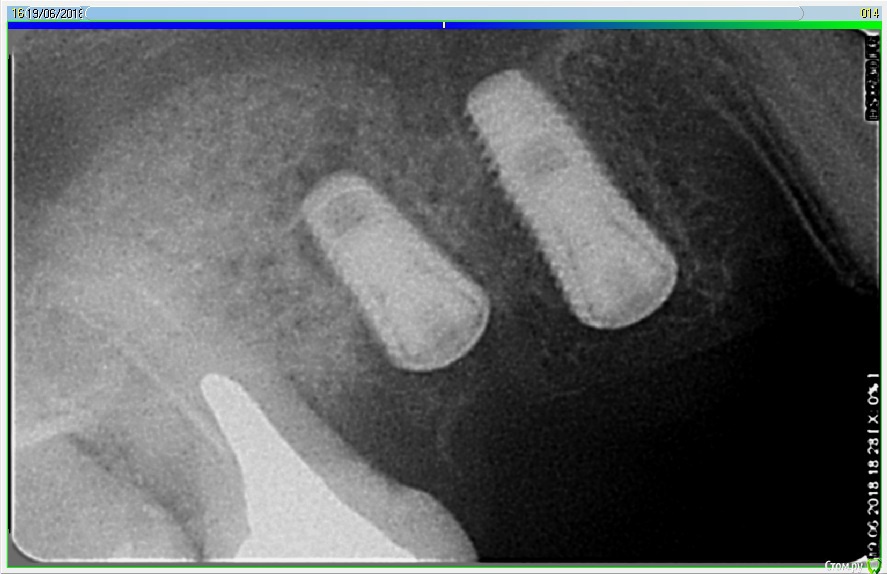

Лералена Опубликовано 14 октября, 2018 Автор Поделиться Опубликовано 14 октября, 2018 На двойном снимке, ситуация до установки мплантатов и после удаления. Ссылка на комментарий

Лералена Опубликовано 8 января, 2019 Автор Поделиться Опубликовано 8 января, 2019 (изменено) Подскажите пожалуйста, правильно ли установлены импланты? Картина такая, удалили 14 и 16 зубы, 15 давно нет, удалили 10 лет назад. Поставили импланты не понятно как, вроде как 15 и 16, как сказал врач. Самих имплантов уже нет, удалили на 8 сутки, прошло достаточно времени чтобы повторить операцию. Но, прежде хочется понять, стоит идти к этому врачу, зовет бесплатно устранить все, или все же не стоит рисковать и обратиться к другому. Диагноз после удаления имплантов звучал как Периапикальный абсцесс.Спасибо за ответ! Изменено 8 января, 2019 пользователем Лералена Ссылка на комментарий

Лералена Опубликовано 8 января, 2019 Автор Поделиться Опубликовано 8 января, 2019 (изменено) А вот и сами снимки, если конечно по ним можно что-то сказать. Изменено 8 января, 2019 пользователем Лералена Ссылка на комментарий